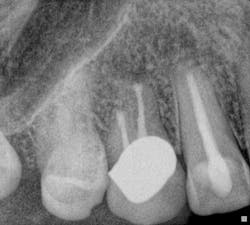

Fig. 8: Retreatment preop radiograph.Note the less-than-ideal technical status of the existing RCT with an incomplete coronal seal.

Fig. 9: Sinus tract tracing with GP. Endodontic treatment was necessary due to the persistence of a buccal sinus tract that can be traced to the radiographic apex of tooth No. 10, despite recent endodontic treatment. Retreatment was performed and the sinus tract persisted, despite the adherence to strict protocols for intracanal disinfection and establishment of a technically satisfactory intracanal seal.

Fig. 10: Retreatment postop radiograph.